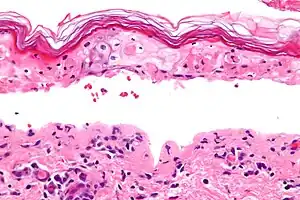

Micrograph of confluent epidermal necrosis. H&E stain. | |

Erythema multiforme major is a form of rash with skin loss or epidermal detachment.